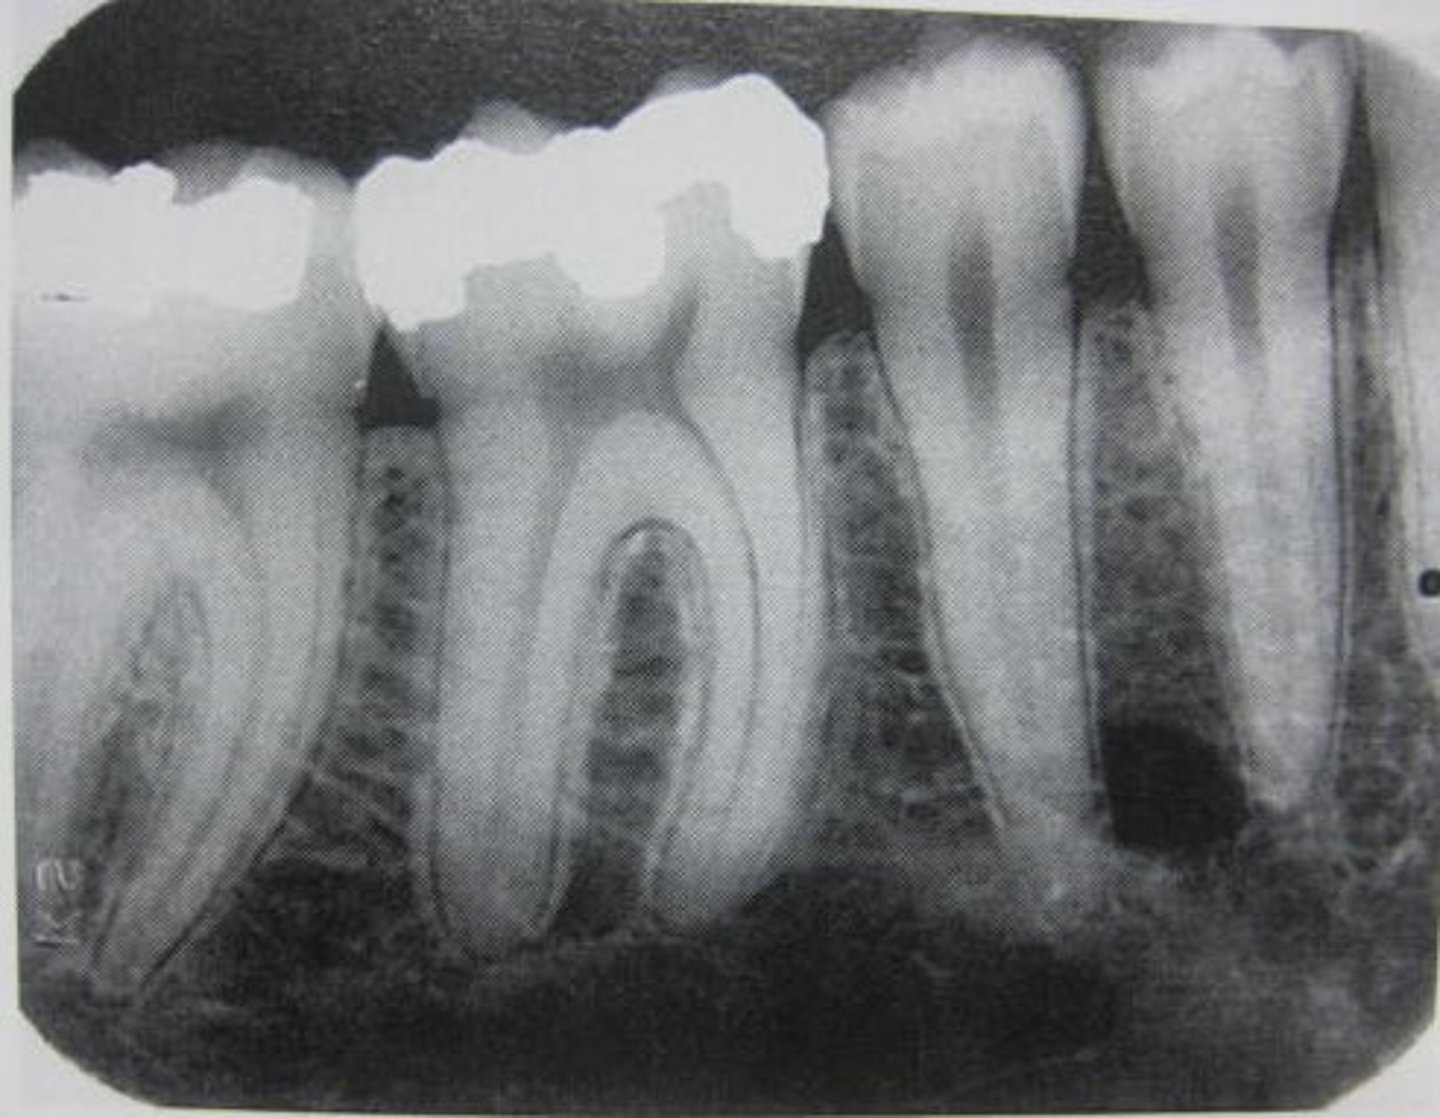

periapical

radiographic image showing the crown, root tip, & surrounding structures

periapical radiographs used to detect:

any abnormalities of the root structure & surrounding bone structure